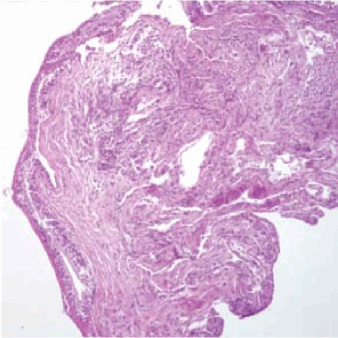

При уретероскопии в средней и верхней трети мочеточников визуализируются множественные тонкостенные кистозные элементы, располагающиеся подслизисто, местами сливного характера, диаметром доходящие до 1 см (рис. 3). Взята биопсия. При гистологическом исследовании: микрокистозная дегенерация мочеточника (рис. 4).

Рисунок 4. Микроскопическая фотография биоптата слизистой мочеточника

Figure 4. Microscopic photograph of the ureteral mucosa biopsy